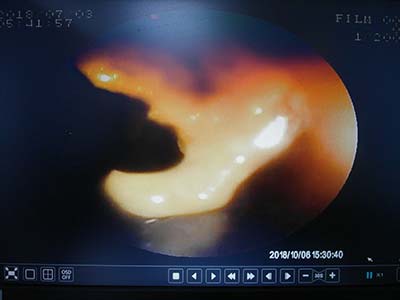

內視鏡下看到食道內的蘋果

以導管輔助將異物取出